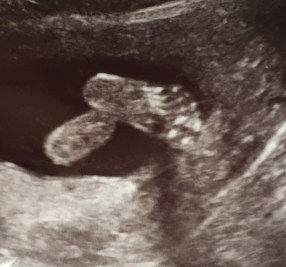

I experienced some mild ‘spotting’ (bleeding) when I was about 7 weeks pregnant and I had a scan in the Early Pregnancy Assessment Department (EPAD/EPAUs) at the hospital. All was fine, the dates matched up and a healthy heartbeat was racing away. I relaxed and enjoyed another 3-4 weeks of pregnancy. I was just over 10 weeks when some mild bleeding started again, I wasn’t too concerned as felt otherwise fine. My 12 week dating scan was booked the week later so I decided not to arrange another early scan via EPADs.

I cannot pretend that my third pregnancy with my son was easy. I was quite detached from it all in the first trimester, trying not to get too close in case the pregnancy was also destined for miscarriage. I was really surprised at the huge relief I felt at our dating scan, seeing that heartbeat ticking away on the screen was a special moment. One friend told me recently that she didn’t want to get ‘too excited’ about her second pregnancy as her first had ended in miscarriage. She wanted to ‘protect her heart’ in case the outcome was the same. This really resonated with me and I am sure it will with some of you who have also been through miscarriage.